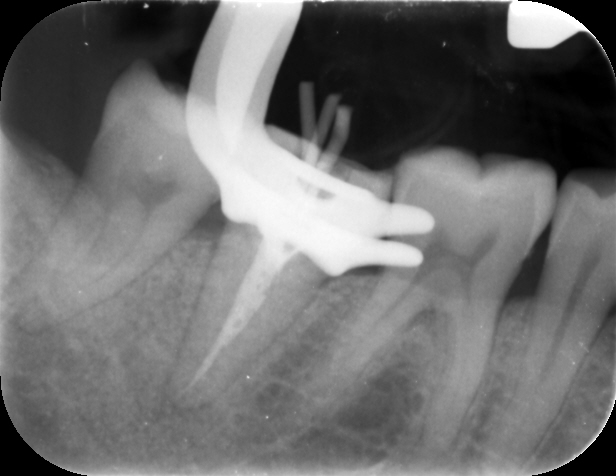

Saving a tooth with laser-assisted endodontics

In this case report, Dr Senthil demonstrates how precise root canal treatment helped to save a tooth and avoid more complex therapy for a patient suffering from advanced caries.